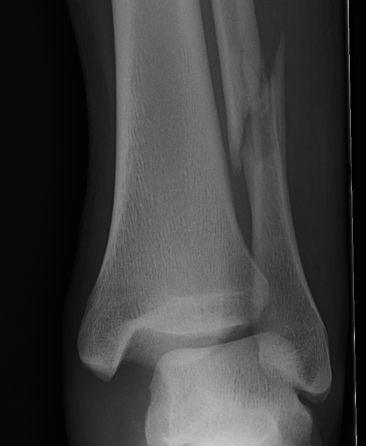

X-ray assessment

3 standard views

AP / Lateral / Mortise

Increased tibio-fibular clear space  Overlap Increased medial clear space

Medial border of the fibula

Lateral border of the posterior tibia (incisura fibularis)

Measured 1 cm above the plafond

Overlap of the fibula and the anterior tibial tubercle

Medial talus to lateral medial malleolus

<5mm AP and mortise

> 6 mm AP view

> 1 mm mortise view

< 4mm

Equal to superior clear space

Syndesmotic injury Syndesmotic injury

Deltoid ligament injury

Lateral talar shift

Ankle AP Xray Syndesmotic Measurements Ankle Mortice Xray Syndesmotic Measurements Mortise

Lateral talar shift / increased medial clear space / deltoid ligament injury